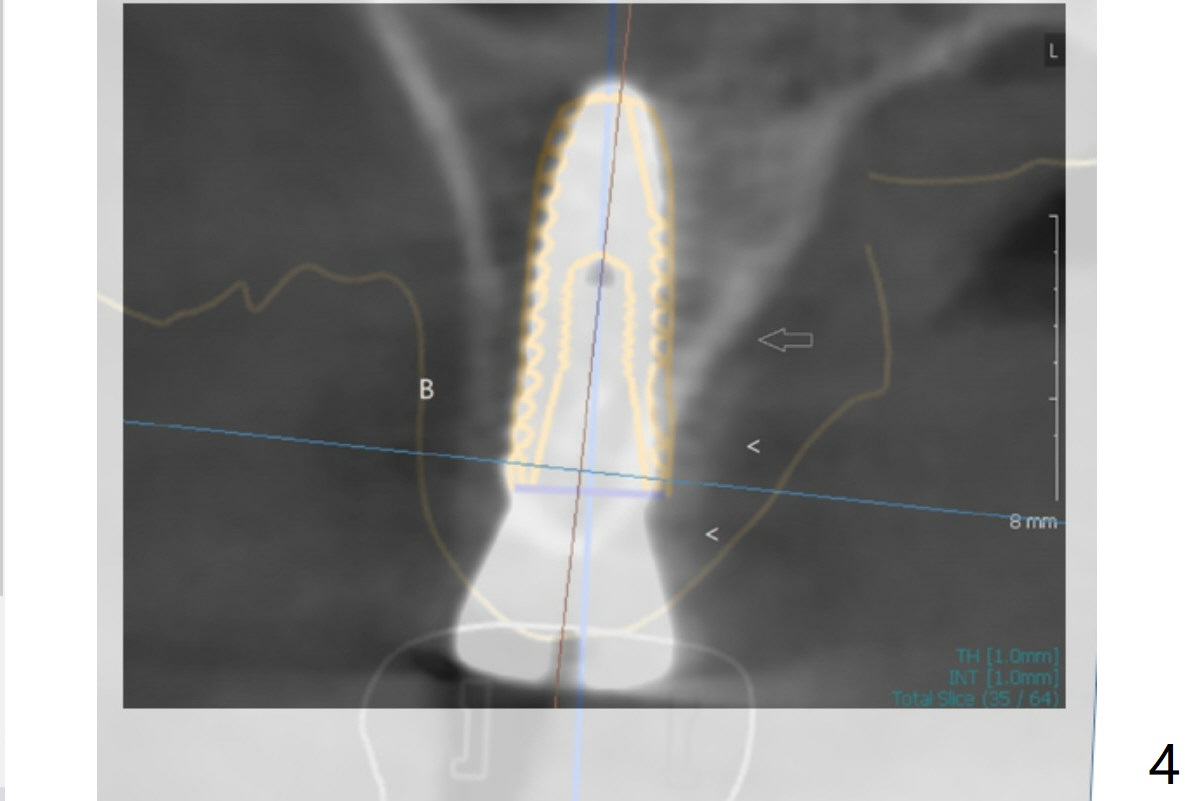

With understanding tissue punch and engagement of drill as much as possible into guide sleeve before pressing pedal, guided surgery is accomplished with confidence (Fig.1,2).  With undersized drilling, there is no thread exposure palatally, when a flap is raised.  Vanilla graft is placed, since it has been prepared before incision.  No membrane is used.  It appears that the palatal bone expands while the implant is being placed.  CBCT taken 10 days postop shows apparently the coronal end of the palatal plate (Fig.3 arrows) and bone graft (<).  Although postop pain is slightly more associated with incision for bone graft, the wound heals with periodontal dressing 10 days postop.

Again thank you for sharing your valuable experience and it is quite interesting that bone expands when we did the undersized drilling.  I just double checked the planning and found out that the original design had palatal thread exposure but when I see the screenshot, it is not. That is quite interesting and we have not heard about that quite yet. I mean the fact that undersized drilling has saved bone graft.  Let's try in other applicable cases again and it is verified as working, this could be a great idea to minimize the possibility of unnecessary bone grafting.  Jennifer overlaps the images of the design and the postop CT (Fig.4).